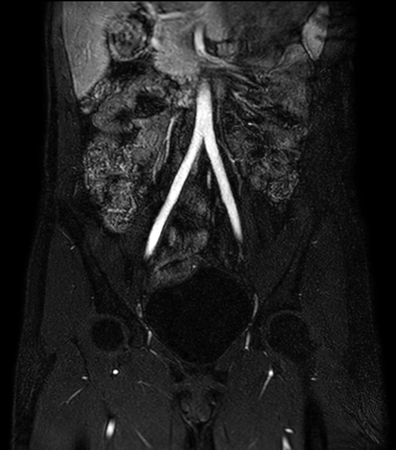

Non-subtraction MR Angiography

Utrecht Medical Center, The Netherlands